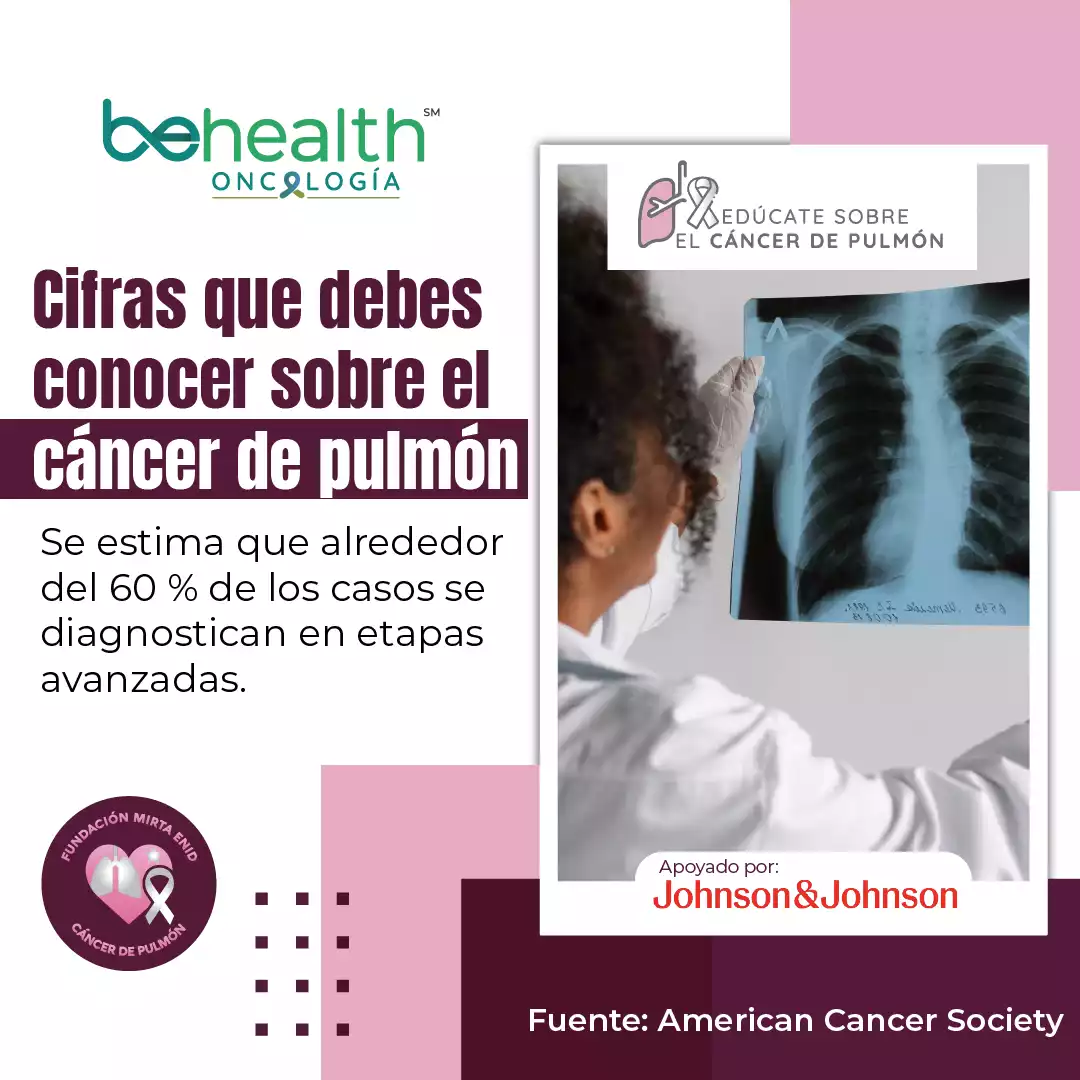

Esta iniciativa busca generar mayor conciencia sobre uno de los cánceres más prevalentes en Puerto Rico, que ocupa el tercer lugar entre los más diagnosticados en hombres y mujeres, y es la segunda causa principal de muerte por cáncer, según la Asociación Puertorriqueña del Pulmón.